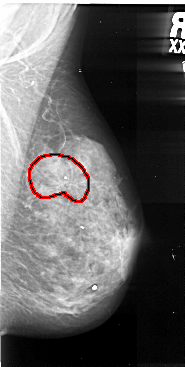

A_1058_1.RIGHT_CC

RIGHT_CC LINES 5056 PIXELS_PER_LINE 2686 BITS_PER_PIXEL 16 RESOLUTION 42 OVERLAY

FILE: A_1058_1.RIGHT_CC.OVERLAY

TOTAL_ABNORMALITIES 1

ABNORMALITY 1

LESION_TYPE MASS SHAPE ARCHITECTURAL_DISTORTION MARGINS SPICULATED

ASSESSMENT 5

SUBTLETY 5

PATHOLOGY MALIGNANT

TOTAL_OUTLINES 1

BOUNDARY